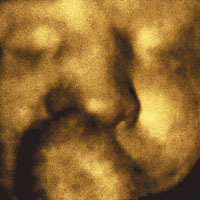

FAN › UNA FOTóGRAFA ELIGE SU IMAGEN FAVORITA: PAULA GRANDIO Y UNA IMAGEN 3D DE UN BEBé POCO ANTES DE NACER

Al final, la foto que elegí es un poco menos conocida... es una foto que me mandó por mail mi amigo Juan Solanas.

Ahora me doy cuenta: las dos imágenes que estuve considerando son un poco proféticas, muestran algo inaccesible. Este es el retrato de Dante antes de nacer.

La foto me llegó en un attachment-panza que tenía dos fotos que, me imagino, son casi simultáneas: en una está Paula, la madre, mostrando su panza feliz con el pijama de Juan –o espero que ése sea el pijama del padre...–. En el otro archivo, que se llama Bebito-foto-3Dwater.jpg., estaba Dante chupándose el dedo. Tiene los ojos cerrados; me pregunto si ya los habrá abierto o si le molestará alguna luz... ¿Cómo habrán hecho? Creo que la foto es hermosa, y como Juan no puede dejar de ser un gran fotógrafo, meticuloso, la foto está dosificada, no es tan inocente. En todo caso, después de lagrimear un poco lo llamé y me chusmeó las opiniones de las abuelas, de los tíos... naturalmente yo también quise opinar y nos ponemos a discutir, que si tenía la nariz de la madre, que a quién se parecía... y de golpe me veo opinando de alguien que no conocía, que todavía no nació...

Damián Solanas, que hoy tiene dos meses de edad, unas diez semanas antes de nacer.